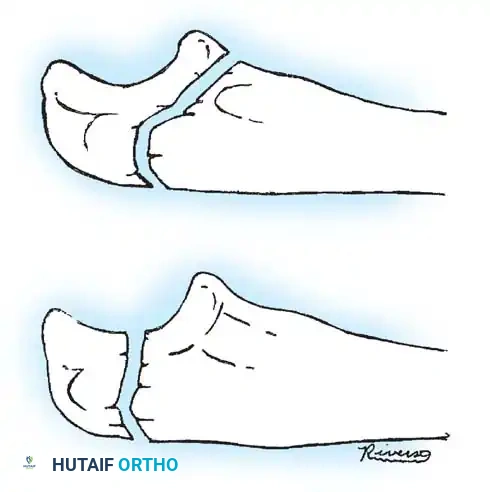

In cases of chronic radial head dislocation (often missed acutely or associated with plastic deformation of the ulna), simple open reduction is insufficient. The Hirayama Technique utilizes an ulnar osteotomy to overcorrect the angular deformity, thereby pulling the radial head back into the joint via the interosseous membrane.

TECHNIQUE 33-5: Osteotomy of the Ulna (Hirayama et al.)

- Preparation: Inflate a pneumatic tourniquet. Make a posterolateral skin incision exposing the radiohumeral joint and proximal third of the ulna. Excise intra-articular scar tissue.

- Osteotomy: Perform a subperiosteal osteotomy of the ulna 5 cm distal to the olecranon.

- Distraction and Angulation: Distract the osteotomy by 1 cm to lengthen the ulna.

- For Anterior Dislocation: Correct by posterior angulation of the ulna.

- For Lateral Dislocation: Correct by medial angulation of the ulna.

- Fixation: Secure the osteotomy with a metal plate bent to approximately 15 degrees. Ensure the radial head rests perfectly within the radial notch of the ulna without excessive radiocapitellar pressure.

- Closure: Approximate the anconeus. Do not repair the annular ligament, as this can restrict rotation.

- Postoperative Care: Apply a plaster splint in 90 degrees of flexion and full supination for 4 weeks, followed by aggressive active range of motion.

Fig. 33-36 Overcorrection with posterior convexity for anterior dislocation.

Fig. 33-37 Overcorrection with medial convexity for lateral dislocation.